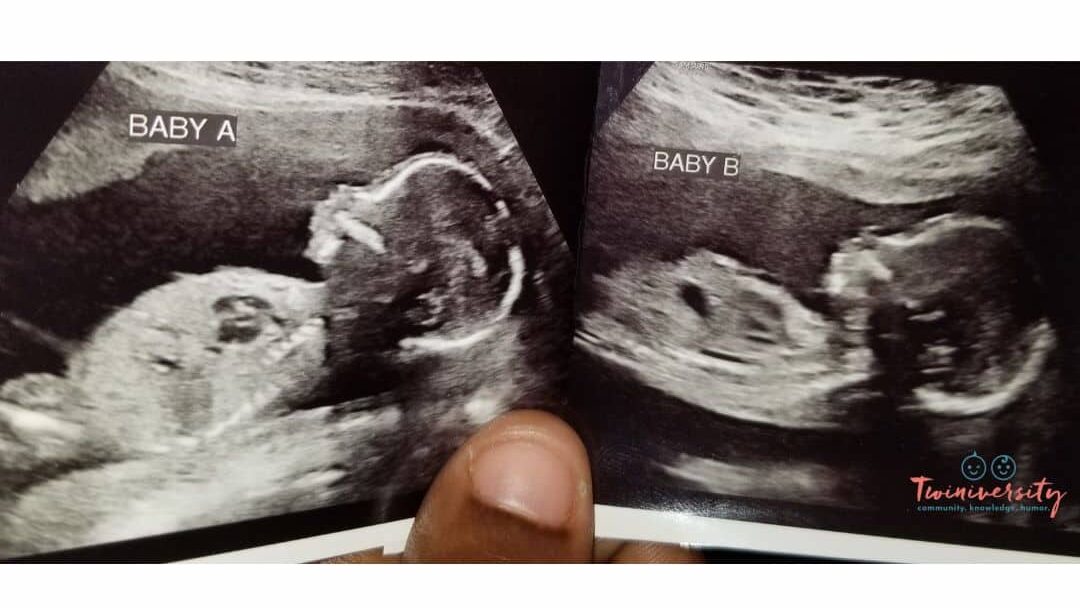

Imagine going for your 20-week ultrasound (halfway into your pregnancy), so excited to see your baby, and finding out that your baby is actually BABIES? It doesn’t happen super often, but sometimes a second baby goes undetected in early pregnancy. Most pregnant women find out its twins at their 8-week ultrasound, or even earlier. But see what twin moms had to say about finding out it was twins at a later ultrasound!

Let’s put it this way, nothing is truly impossible. It is highly unlikely that twins might go undetected. But, as you can see, it is certainly possible that you might have another little surprise in there and find out at a later ultrasound.

Again, it’s rare but possible to experience a “hidden twin” during your pregnancy. Mostly, the imaging available nowadays will pick up a second baby pretty early on. But a twin can be overlooked, especially if your provider isn’t looking for a twin at first glance.

Twins can typically be detected on ultrasound during the first trimester, usually around 6 to 8 weeks of gestation. In some cases, healthcare providers may be able to identify the presence of twins even earlier, especially with advanced ultrasound technology. The ability to visualize twins on an ultrasound depends on factors such as the clarity of the image, the position of the embryos, and the experience of the ultrasound technician.